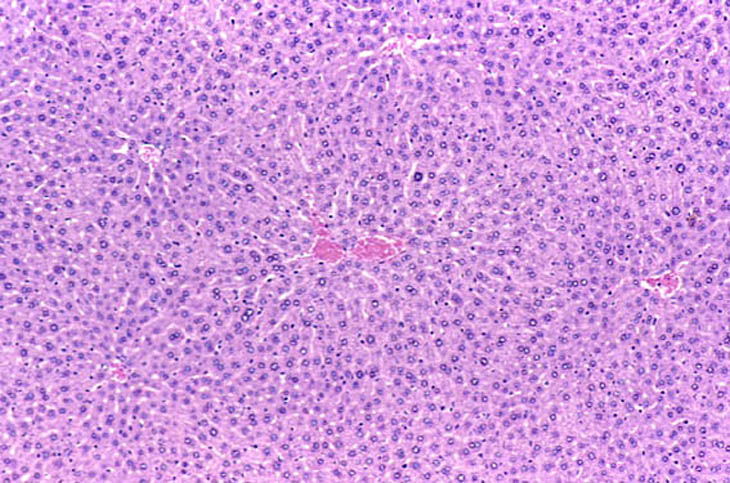

Immersion fixed liver following an overnight fast. Fixative was 10% NBF.